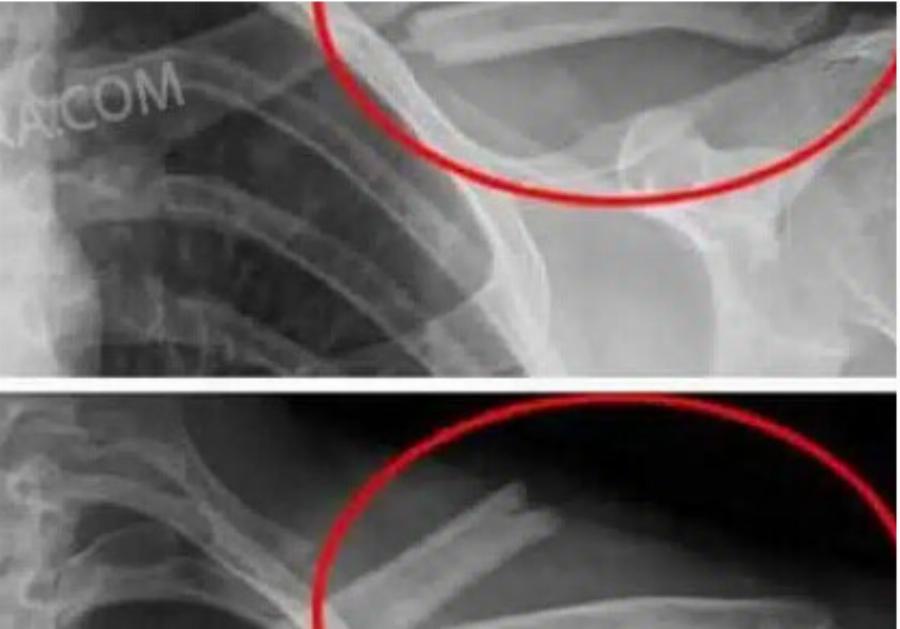

Αποδυναμώνουν τα οστά: Η υψηλή πρόσληψη νατρίου που περιέχουν πολλά από αυτά , μειώνει το ασβέστιο, αυξάνοντας τον κίνδυνο οστεοπόρωσης.